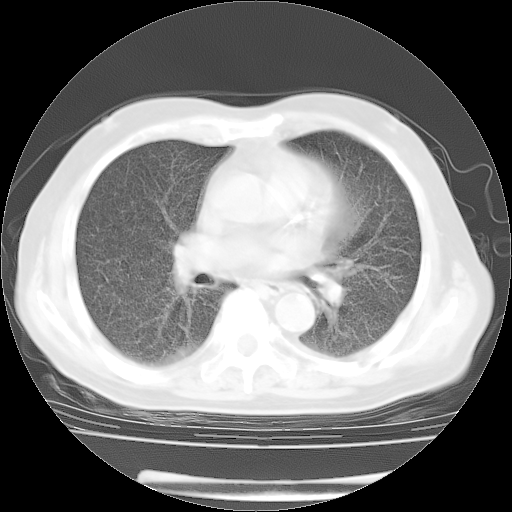

4月28日肺部CT——再次出现类似去年5月9日——磨玻璃样、间有“粟粒样”改变。